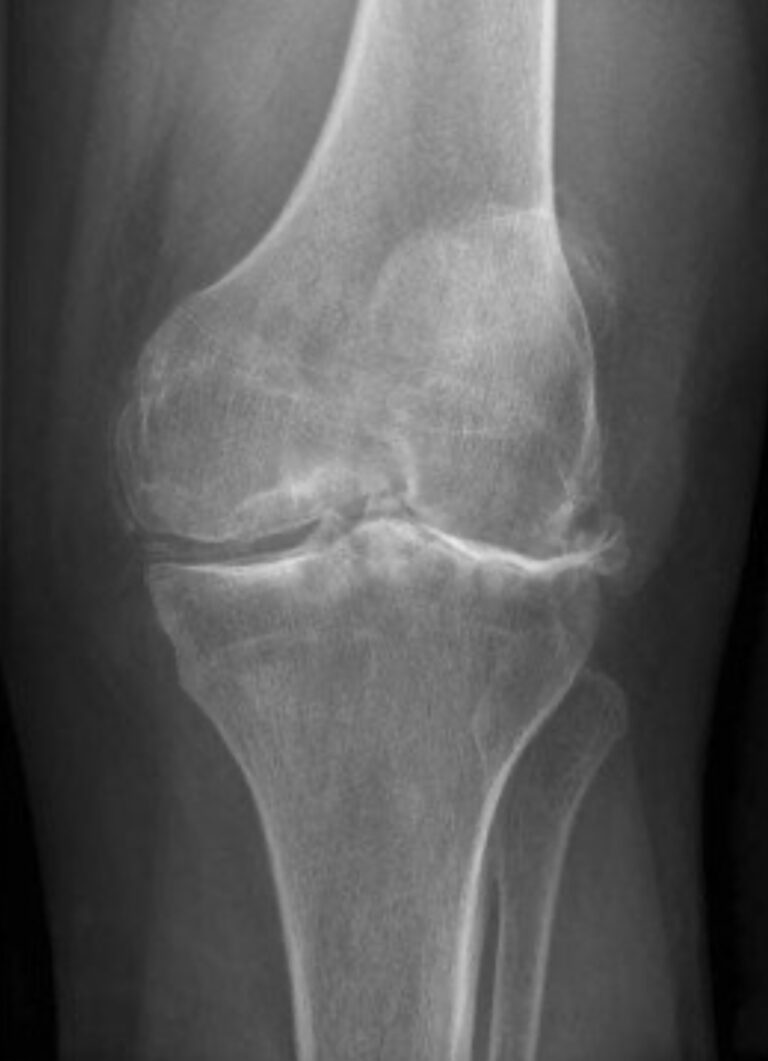

Learn about genicular artery embolization for knee osteoarthritis, and other minimally invasive treatment options to help you find relief and improve your quality of life.